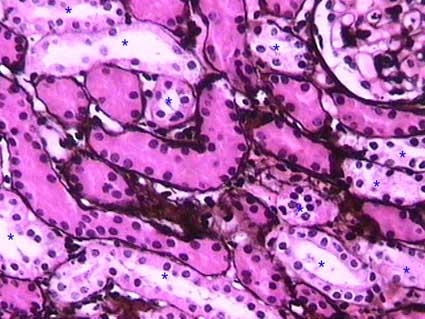

Figure 4. The silver stain emphasizes the basement membranes of tubules and it allows us to delineate the contours very well. The prominent eosinophilic cytoplasm of the proximal tubules contrasts with the clearer and less abundant cytoplasm of the distal tubules (asterisks). (Methenamine-silver stain, X200).